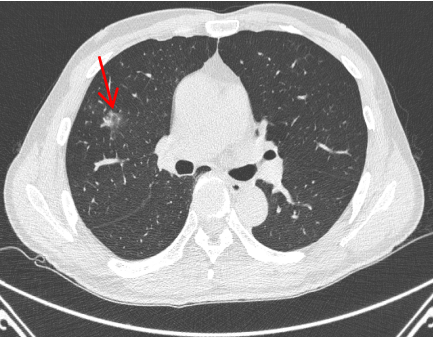

肺癌是我国发病率和死亡率最高的恶性肿瘤,75%的患者确诊时已属晚期,早诊早治是提高生存率的关键。随着低剂量螺旋CT的普及,越来越多的肺小结节被早期发现,如何实现精准、微创、根治性治疗成为临床热点。

CT发现结节